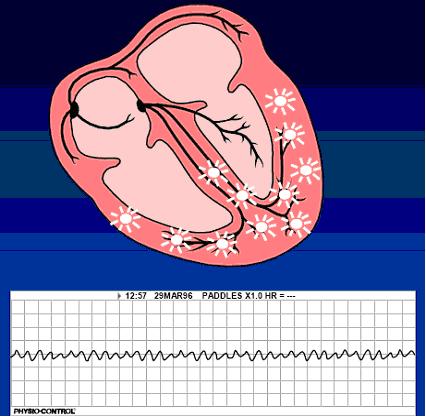

Taşikardi dakikada kalbin atışının yüzün üzerinde ki sayısı şeklinde tanımlanmaktadır. Uyarılar Keith Flack sinüsü düğümü nedeniyle oluyorsa, sinüs taşikardisi denilir. Böyle durumlarda sadece normal ritim hızlanır. Özellikle de asabi insanlarda ve ya ateşlenme sırasında, aşırı heyecanlanıldığın da ve ya zorlanma söz konusu olunca meydana gelen, genelliklede önemli olmayan belirtilerdir. Fakat şok vaziyetinde ve de tiroid bezlerinin çok fazla çalıştığı durumlarda da( hipertiroyidi) rastlanmaktadır. Birde tüm kalp hastalarında görülmektedir.

Elektrokardiyogram ile de doğrulanmaktadır. Eğride ritmin 100 dakikanın üzerinde hızlanması; fakat düzenlidir ve de sinüsten kaynaklanır. Tüm QRS karmaşasının öncesinde, normal P kulakçığın dalgası gelmektedir.